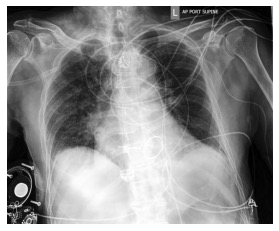

Automated diagnosis prediction from medical images is a valuable resource to support clinical decision-making. However, such systems usually need to be trained on large amounts of annotated data, which often is scarce in the medical domain. Zero-shot methods address this challenge by allowing a flexible adaption to new settings with different clinical findings without relying on labeled data. Further, to integrate automated diagnosis in the clinical workflow, methods should be transparent and explainable, increasing medical professionals' trust and facilitating correctness verification. In this work, we introduce Xplainer, a novel framework for explainable zero-shot diagnosis in the clinical setting. Xplainer adapts the classification-by-description approach of contrastive vision-language models to the multi-label medical diagnosis task. Specifically, instead of directly predicting a diagnosis, we prompt the model to classify the existence of descriptive observations, which a radiologist would look for on an X-Ray scan, and use the descriptor probabilities to estimate the likelihood of a diagnosis. Our model is explainable by design, as the final diagnosis prediction is directly based on the prediction of the underlying descriptors. We evaluate Xplainer on two chest X-ray datasets, CheXpert and ChestX-ray14, and demonstrate its effectiveness in improving the performance and explainability of zero-shot diagnosis. Our results suggest that Xplainer provides a more detailed understanding of the decision-making process and can be a valuable tool for clinical diagnosis.